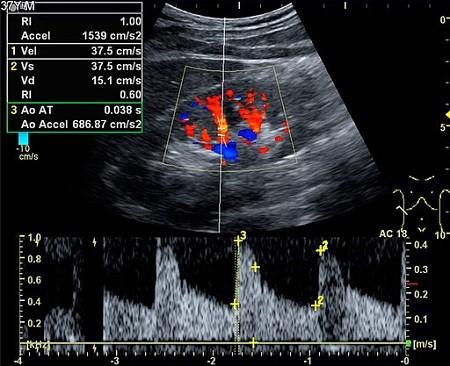

The sound waves may also be converted to colour pictures on a screen so that flow can be seen through the arteries or veins (colour Doppler) - as below.

Colour Doppler ultrasonography

By Mikael Häggström [CC0] (Own work), via Wikimedia Commons

The images below are produced from a Doppler scan of the kidney.

Kidney ultrasound scan

By Kristoffer Lindskov Hansen, Michael Bachmann Nielsen and Caroline Ewertsen [CC BY 4.0 (https://creativecommons.org/licenses/by/4.0)], via Wikimedia Commons